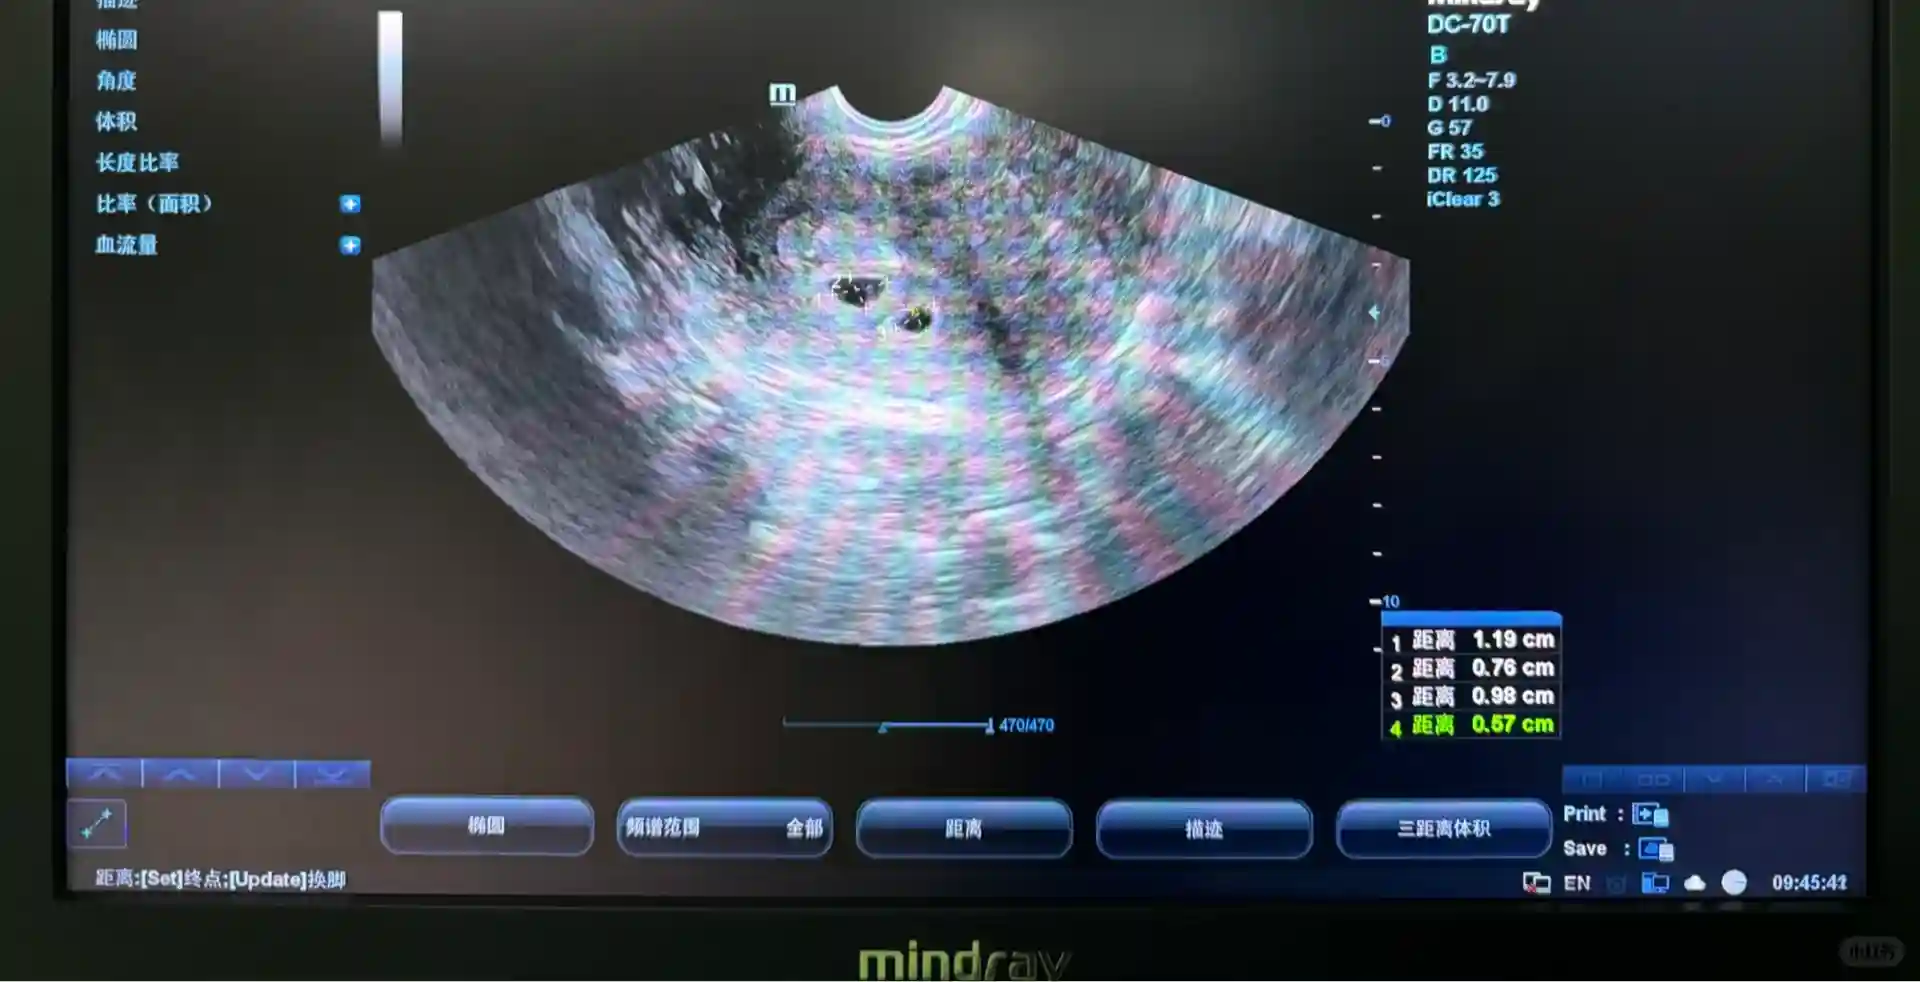

5⃣️移植后,胡主任给我开了黄体酮和肝素。看我心态良好,胡主任也依然不断地鼓励我,每次问诊检查都是在肯定我们病患所作出的努力和付出。移植后的两周,我是直接去医院验HCG得知成功怀上,第一时间就和胡主任报了喜~后面几次例行检查,hcg翻得又快又好,胡主任当即说了一句“是不是怀了双胎呀?”,当时我还不敢相信。没成想再到后面拍B超,显示有2个胎心胎芽的时候,再一次折服于胡主任的专业。